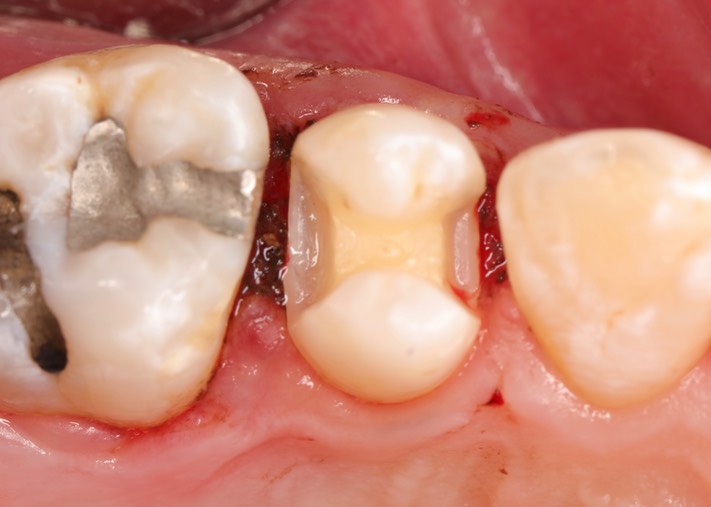

R V Tucker Club #44

Photos of Clinical Operations

Dr. May Chang’s cases